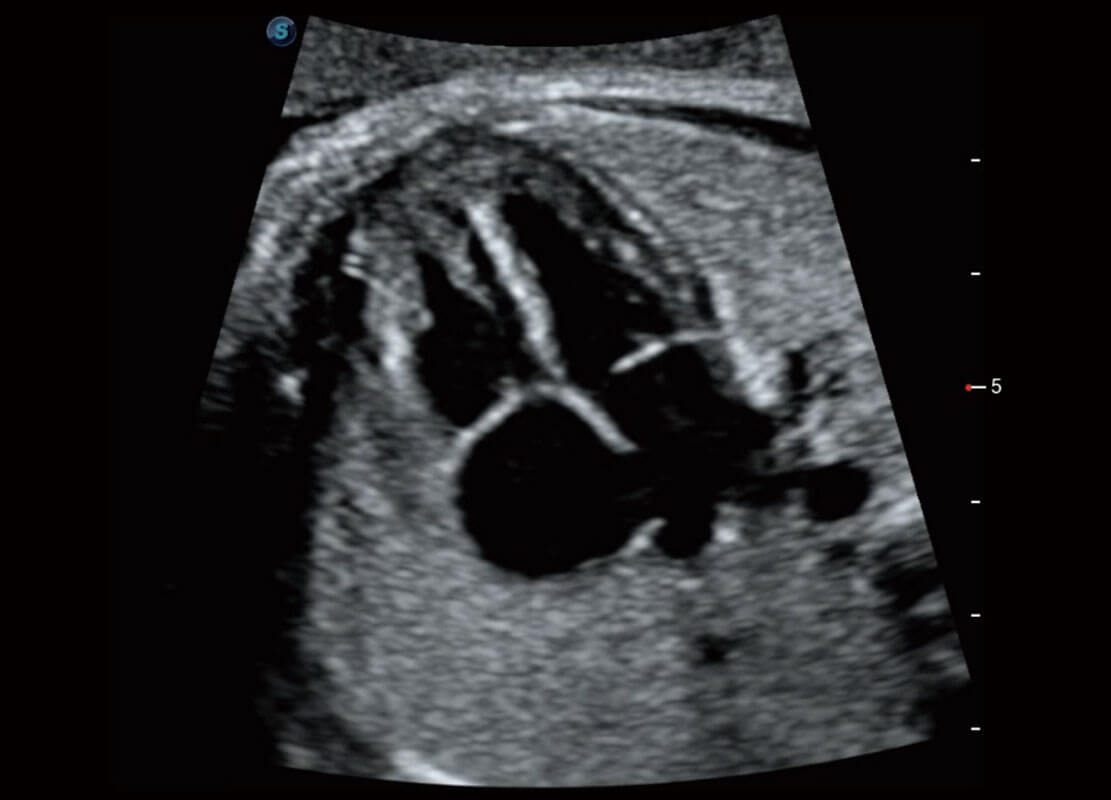

P60搭載一系列胎兒心臟成像技術(shù),實(shí)現(xiàn)精細(xì)的胎兒心臟評(píng)估。

四腔切面

四腔心血流

右室雙出口

胎心容積成像